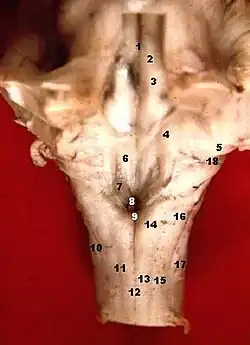

Human caudal brainstem posterior view (Colliculus facialis is #3) | |

Axial section of the brainstem (pons) at the level of the facial colliculus- Fourth ventricle. Posterior view. Deep dissection.